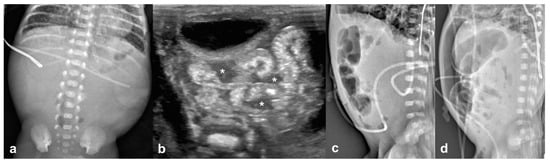

3.2. Imaging Findings

3.2.1. Abdominal Radiographs

3.2.2. Temporal Relation between Abdominal Radiographs and Bowel US